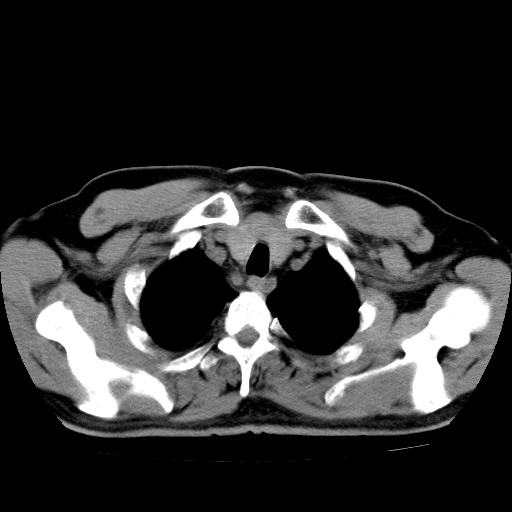

男,54岁,咳嗽,右侧胸痛10天。肺窗>150k,传不了

右肺中心型肺癌并右下肺不张,右侧胸膜纵隔转移。

右中央型肺癌并右肺下叶不张,纵隔内及右胸膜转移,右胸腔积液

考虑   右肺癌伴右下肺部分不张,阻塞性肺炎,纵隔淋巴结增大,右侧胸腔积液其他待排

考虑右肺下叶中央型肺癌并右肺下叶不张,纵隔淋巴结内及右胸膜转移。建议增强。

右下叶大片实变,肺门未见明显肿块影。有胸腔积液和纵隔内肿大淋巴结影。没有增强和肺窗,不好定。

考虑:1、右下叶周围型肺癌伴胸膜、纵隔淋巴转移?